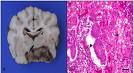

Cancer de Utero El carcinoma endometrial es la neoplasia maligna más frecuente de la pelvis femenina. Cada año se diagnostican alrededor de 40 300 casos nuevos, aunque con gran frecuencia (75%) el diagnóstico se establece cuando la neoplasia está circunscrita al cuerpo del útero, por lo que muchos tumores se pueden curar. Las 7 000 muertes anuales que causa el cáncer de útero significan que... -